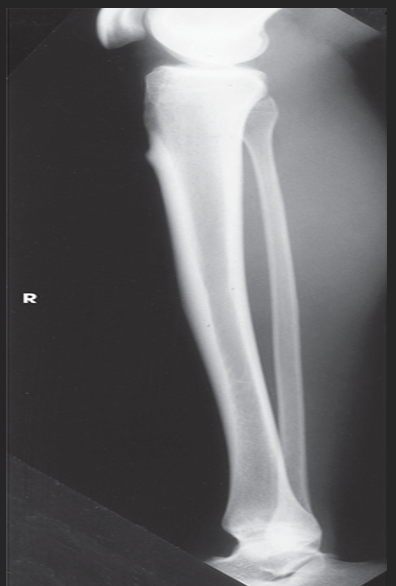

Name this projection.

Lateral leg (tib-fib)

What type of projection is it?

Mediolateral

What SID is used?

48"

Describe the position of the patient.

recumbent onto the affected side; keep the knee slightly flexed to obtain a true lateral

What anatomy must be ⟂ to the IR?

Femoral condyles and patella

Where does the CR enter?

Perpendicular to the midpoint of the leg

What must be seen on the radiograph?

Entire tibia and fibula with adjacent joints

Describe how to evaluate for a true lateral.

Distal fibula superimposed by posterior half of tibia; slight overlap between tibia and fibular head; separation of tibial and fibular bodies (not at ends)